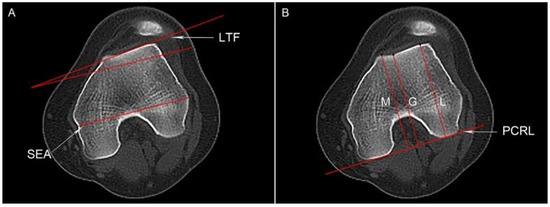

2.3.1. Trochlear Dysplasia